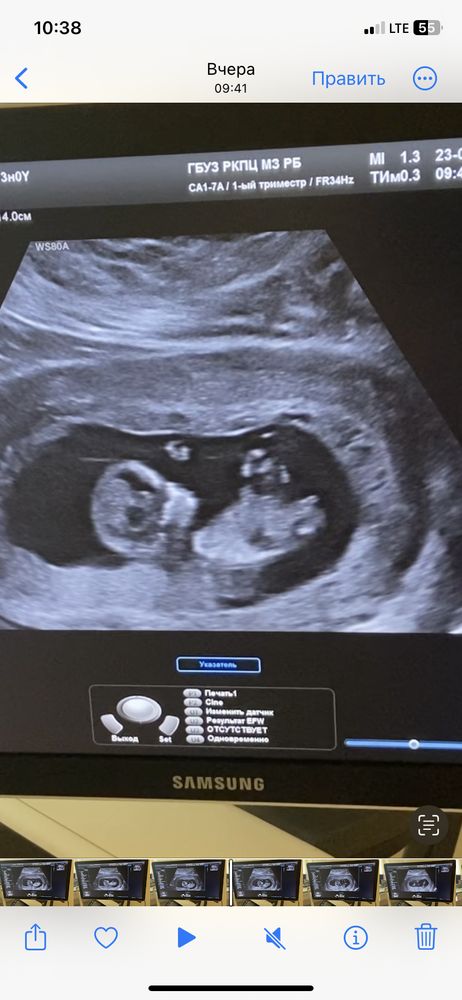

Тоже кажется девочка

похоже что девочка

Марина, у мальчиков отросток больше торчит вверх

Марина, у девочек параллельно,тут больше наклон вверх .Ну лучше конечно в 15-18 неделек перепроверить